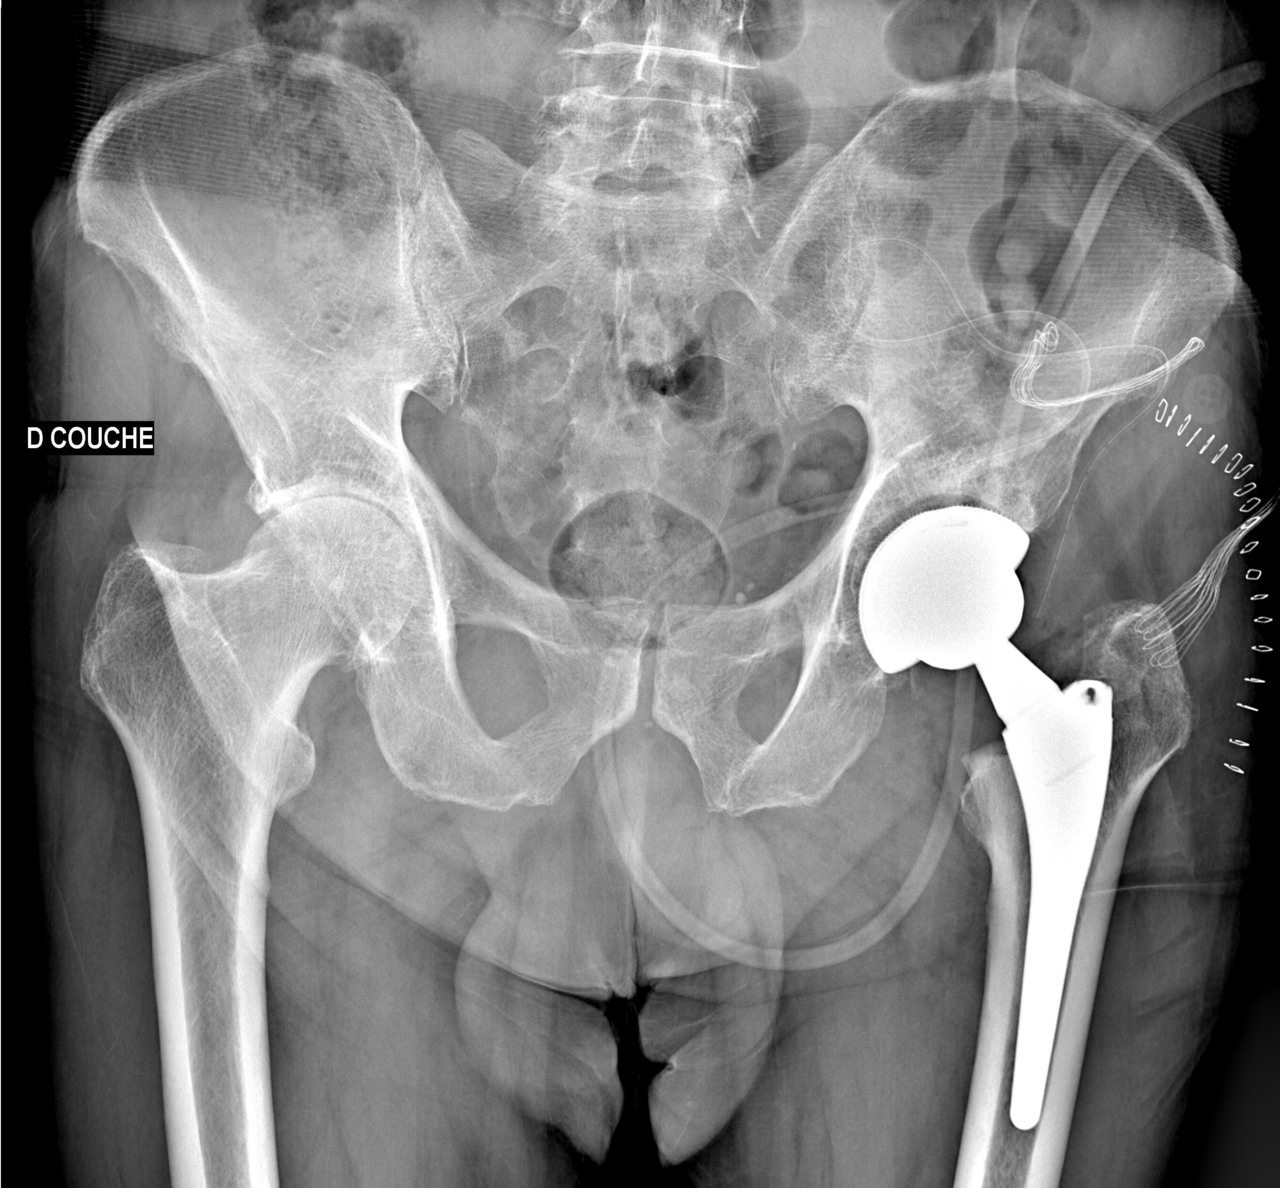

Lorsqu’il sort, il doit s’aider d’une canne que son frère, opéré il y a peu, lui a donnée. Celle-ci le soulage partiellement.